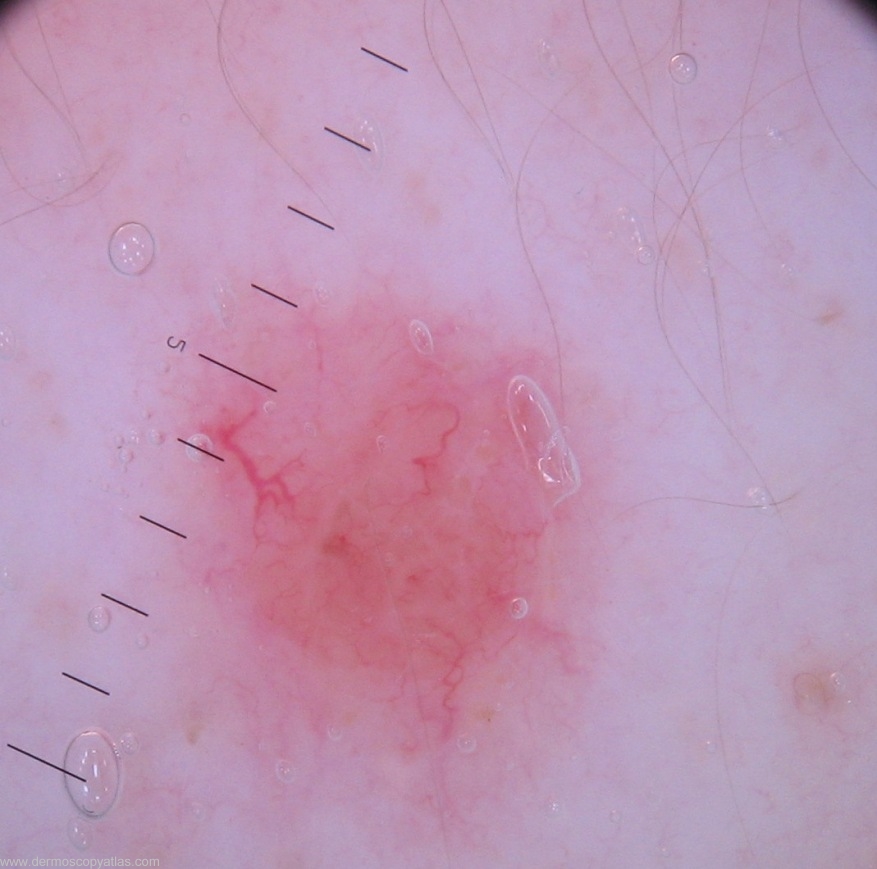

CASE 1. Lesion back, 15 yr old female with type 1 skin and already considerable damage (elastosis and freckling)on exposed areas. Would you consider Banal compound nevus, Clear cell acanthoma, Amelanotic melanoma,Basal cell carcinoma or Other?

Question: What is your clinical diagnosis?

Question: What is your dermatoscopic diagnosis?

Question: What might the histology show?